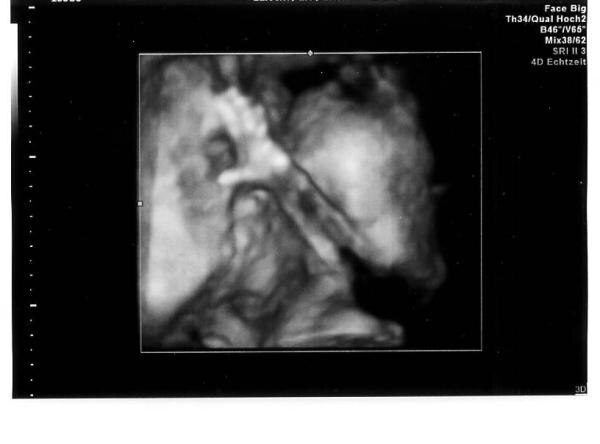

Hatte gestern einen 3D Ultraschall. War unglaublich. Die kleine sieht aus wie ihre große Schwester. Sie hat uns sogar angelacht und gewunken :-) (Ich versuche die Bilder dranzuhängen) Erstaunt war ich über den günstigen Preis. Habe 50 Euro bezahlt, ne DVD und 12 Bilder bekommen. Bei meiner Anfrage wurde mir 75 Euro genannt.... Hab hier auch schon von 100 Euro und mehr gelesen.

Bild zu Gestern 3D Ultraschall! - Forum für März - Mamis